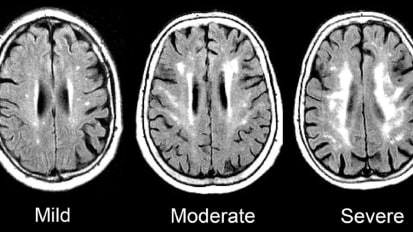

Researchers Identify Inflamed Brain Cells Likely Involved in MS Nerve Degeneration

MRI scans of a patient’s brain showing the chronic active lesions (areas of localized damage marked by arrows within magnified insets) associated with multiple sclerosis (MS). Johns Hopkins Medicine and National Institute of Neurological ...